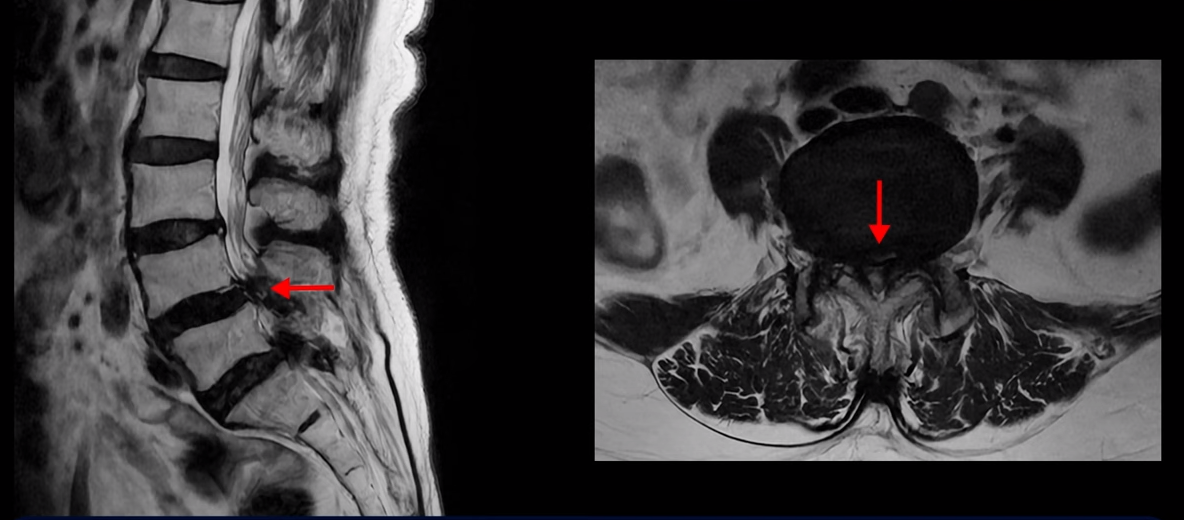

먼저 이분 MRI를 보면서 자세히 설명 드리겠습니다. 보시다시피 허리 여러 마디가 안 좋습니다.

특히 4번 5번에는 심한 중심성 협착이 있어 척추관이 매우 좁아져 있습니다.

5번 1번도 척추관이 좁아져 있고 특히 좌우 신경이 빠져나가는 추간공이 좁아져 있는데 5번 1번 왼쪽 추간공은 많이 좁아져서 신경이 눌리고 있습니다.